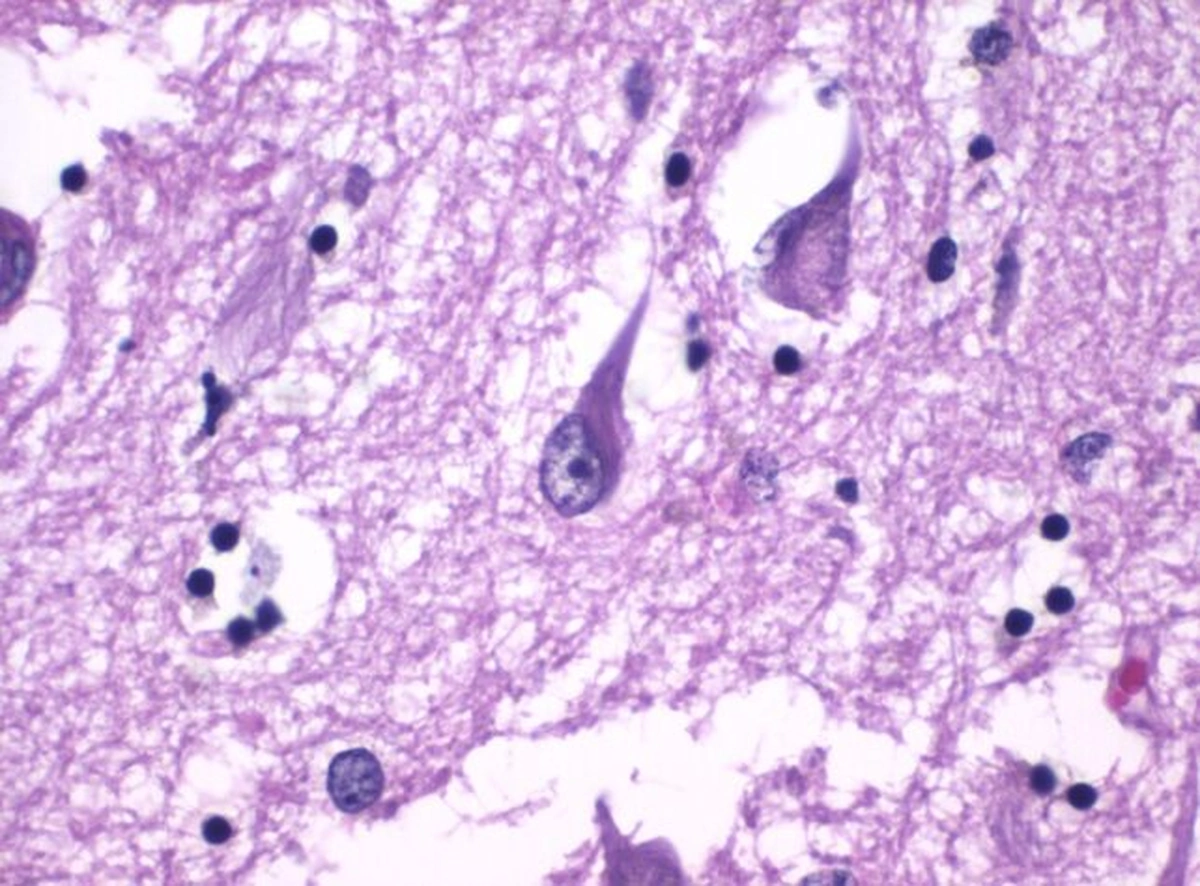

Тау-белки образуют клубки в образце ткани мозга